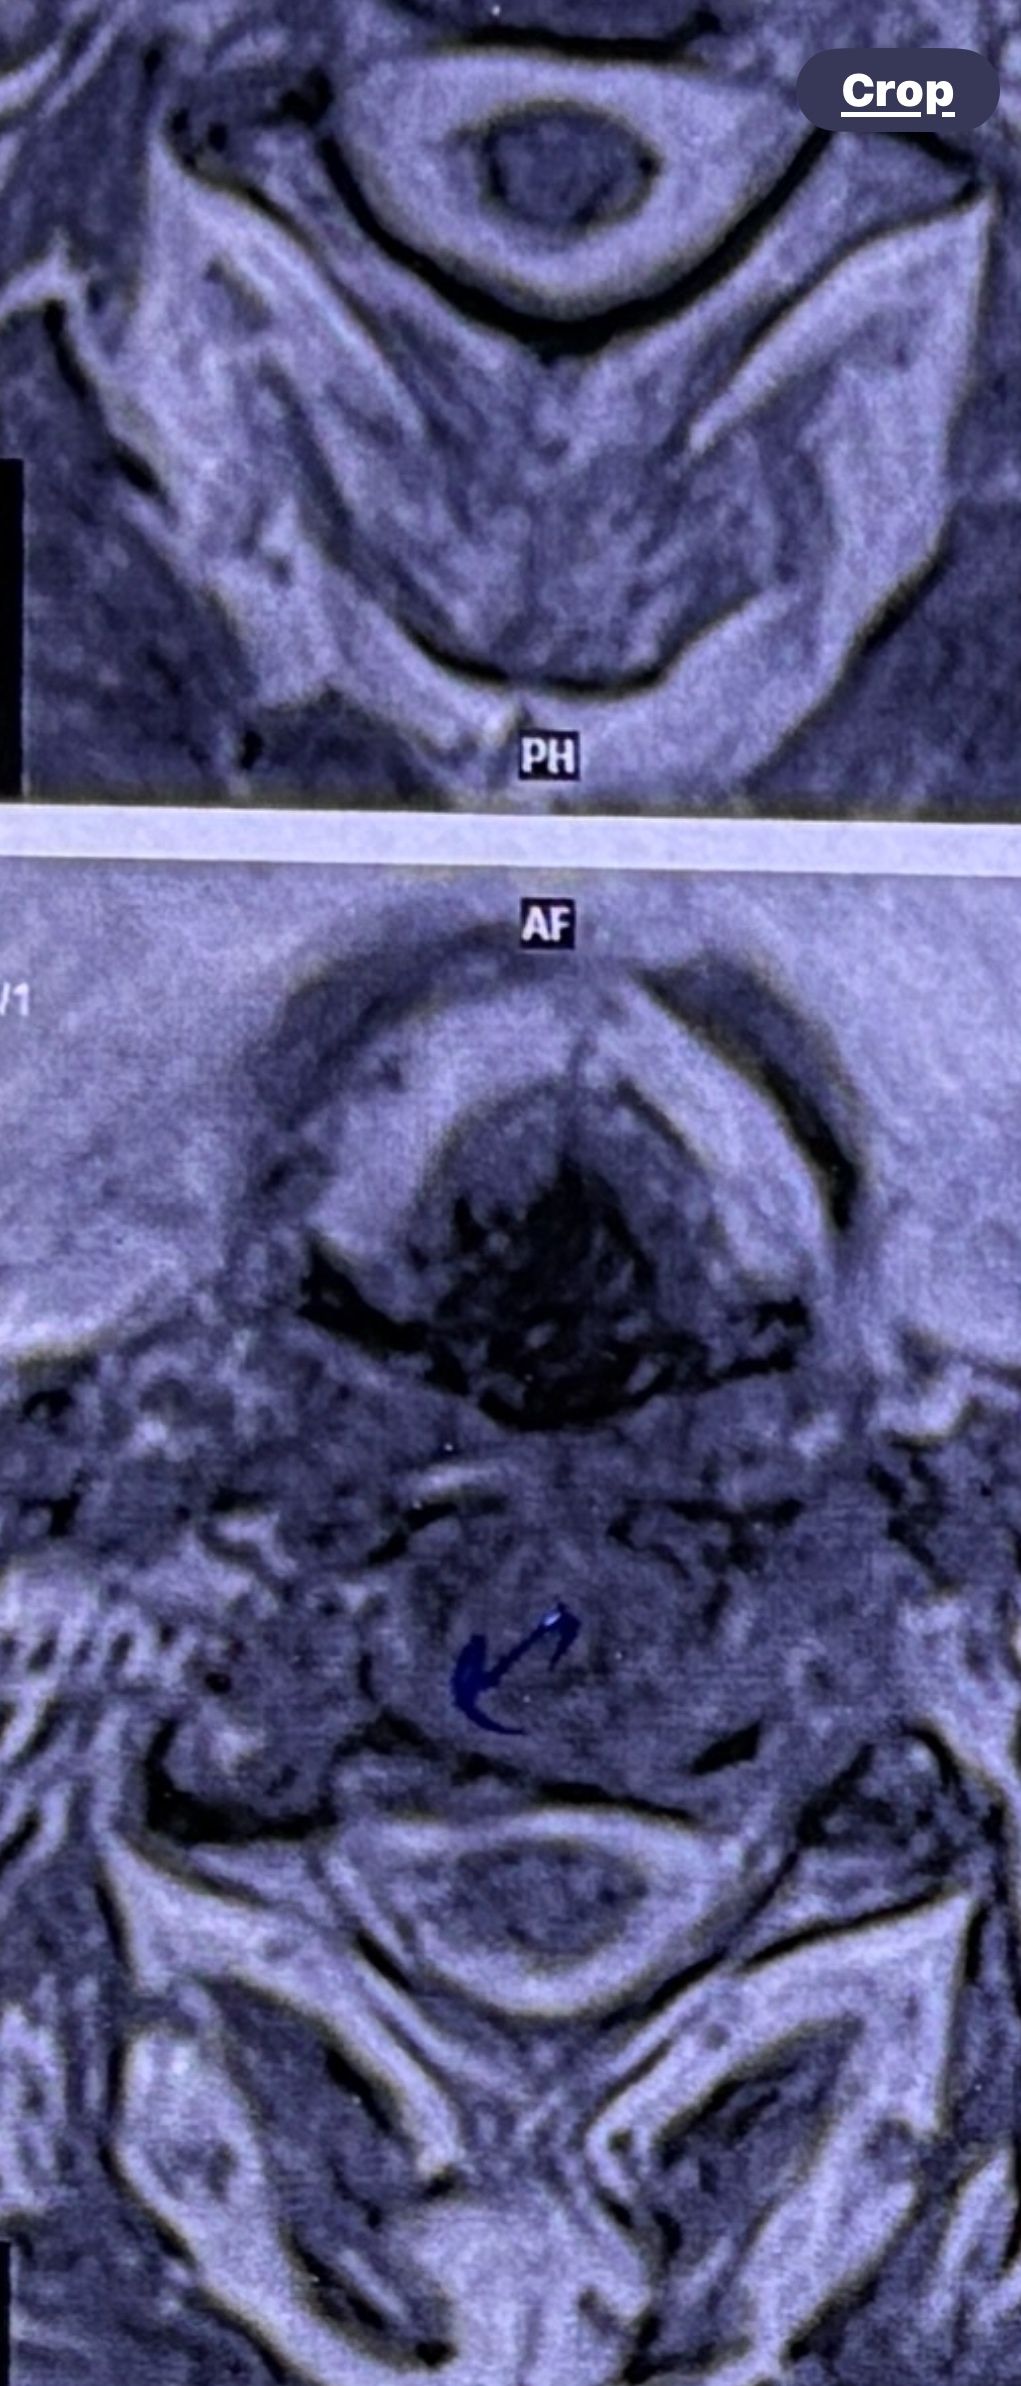

41 years old man presented to my clinic in October 2023 with acute and sever R neck pain with radicular pain to his R upper extremity along C6 dematom since 2 weeks ago. Examination didn’t show any upper motor signs. Was suggested urgent surgery

I ordered EMG/ NCV : showed mild R C6, C7 irritation without any active axonal loss

In his MRI was reported R. para R. IVF Massive extrusion. I decided to control his pain and manage this patient with reevaluation of patient every other session. For 5 sessions i just used acupuncture and laser and IFC and mild adjustments to his R. T3-T7 and mild arthosteem to above and below involved segment. Cervical adjustment considered contraindicated for this patient. From session 6th- 8th i started to use mild/gentle cervical decompression. He used soft cervical collar all the time. His pain decreased by 80 percent

I gave him cervical traction pump to be used 3-5 times per day at home for the next 3 months and i released the patient. He was evaluated every week once for one month and after that every 2 weeks. After 3 month I repeated MRI. Size of the herniated disc was reduced greater than 50 percent. Asked him to do another mri in 6 months

In general: Precise selection of the patients, examination,diagnosis, plan of management, reevaluation and treatment can be done by doctors of chiropractic for the patients with spinal disc herniation and stenosis Moreover giving reasonable time to these kind of patients under direct supervision by their chiropractic doctors can prevent unnecessary surgery. Proper selection of these kind of patients is another important fact that can be done precisely by chiropractors.

MRIs before and after proper management of this patient: